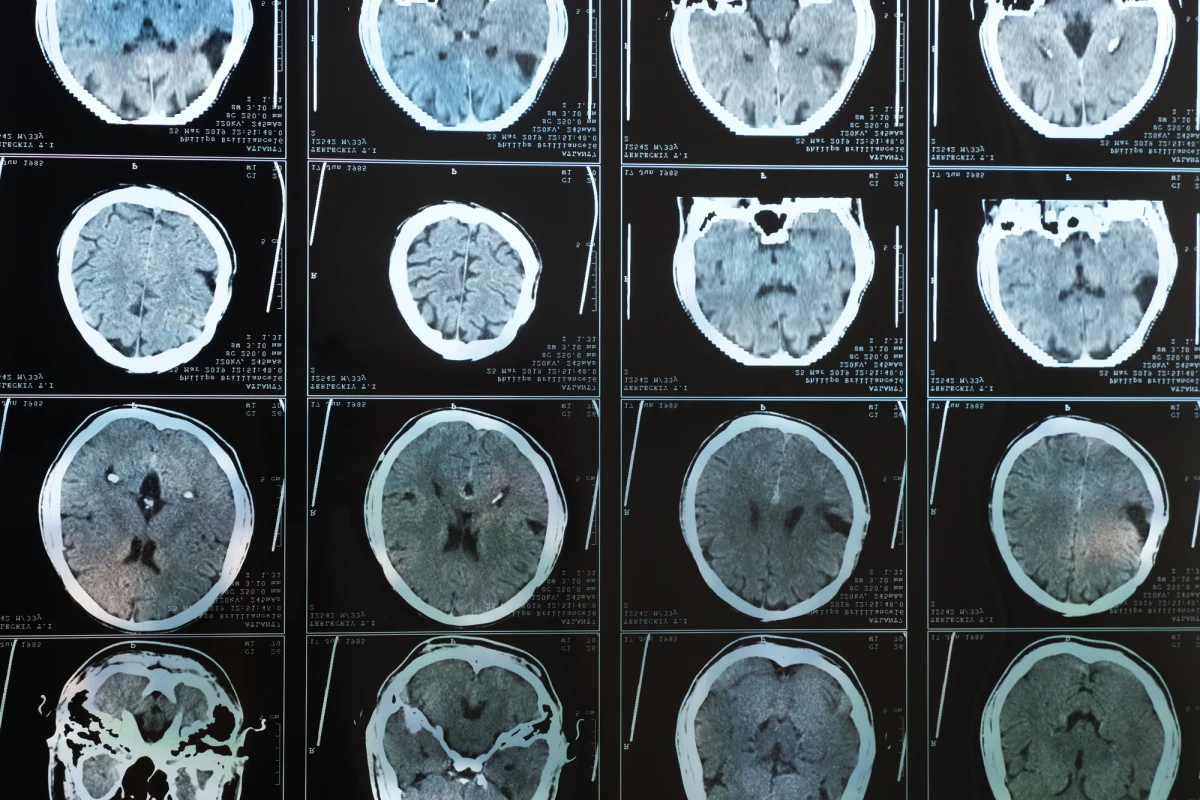

In a new study conducted by a team of US researchers, brain scans from more than 17,000 subjects were analyzed to investigate the association between body weight and cerebral blood flow. The patterns detected were striking, with blood flow across a number of brain regions decreasing relative to a greater body mass index.

The observed decreases in cerebral blood flow were particularly noted in five key brain regions relevant in subjects with Alzheimer’s disease – the temporal lobe, parietal lobe, hippocampus, posterior cingulate, and precuneus.